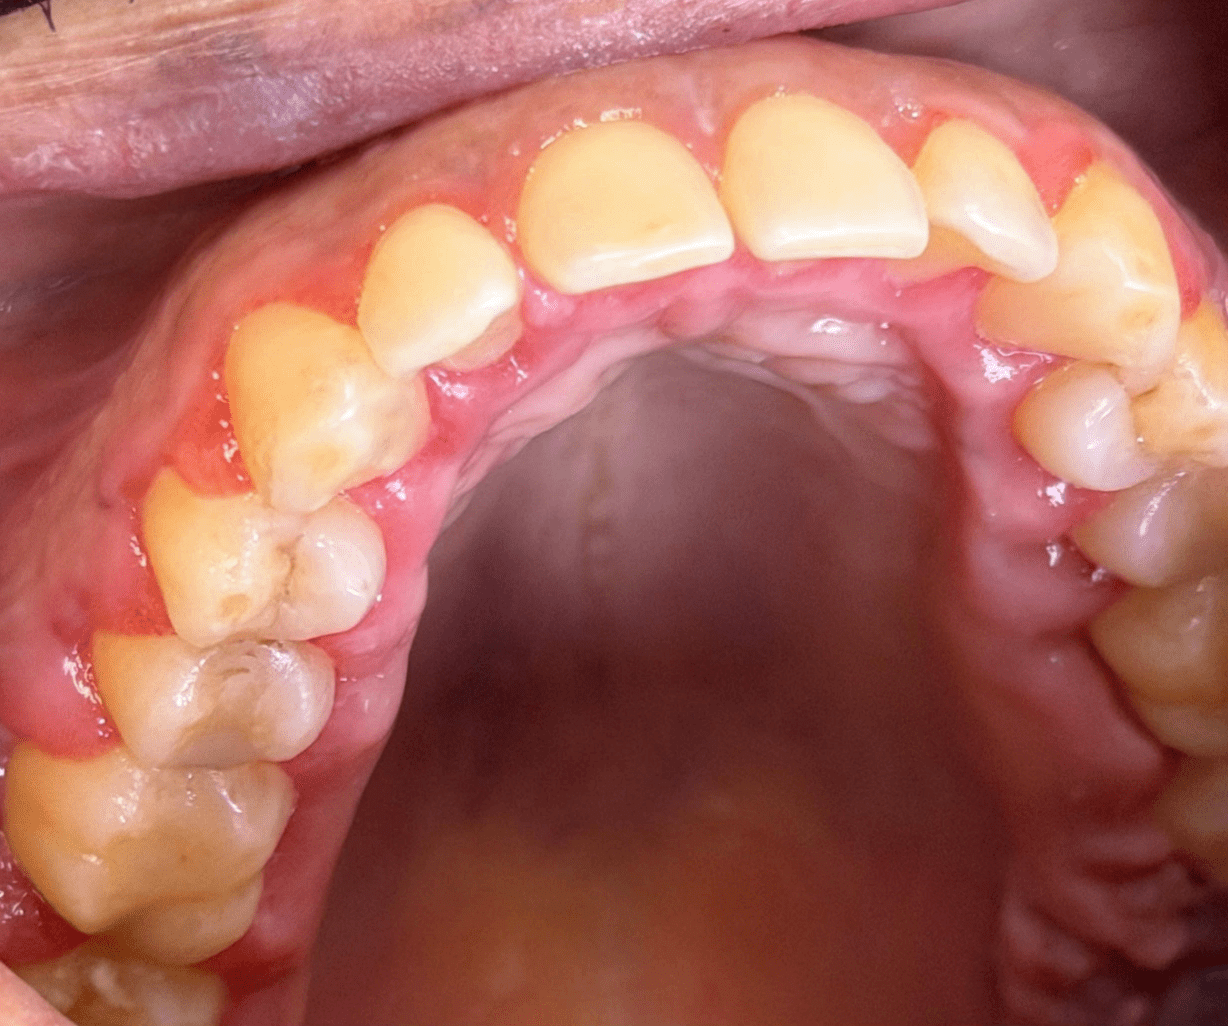

Initial Findings: Increased probing depths, bleeding, and bone loss compared to previous exams. The patient also exhibited increased halitosis compared to previous maintenance visits. The patient’s clinical findings indicated a periodontitis flare-up and periodontal abscesses from incomplete calculus removal during a recent dental cleaning.

Oral signs occur in approximately 30% of patients with newly diagnosed acute leukemia, though classic findings like gingival enlargement are present in only about 6% of cases.[1][2] Key oral manifestations include:

- Gingival enlargement or hyperplasia (particularly in acute myeloid leukemia with monocytic subtypes)[3][2]

- Spontaneous gingival bleeding and mucosal bleeding[4][2]

- Unexplained periodontal deterioration despite previous stability[6]